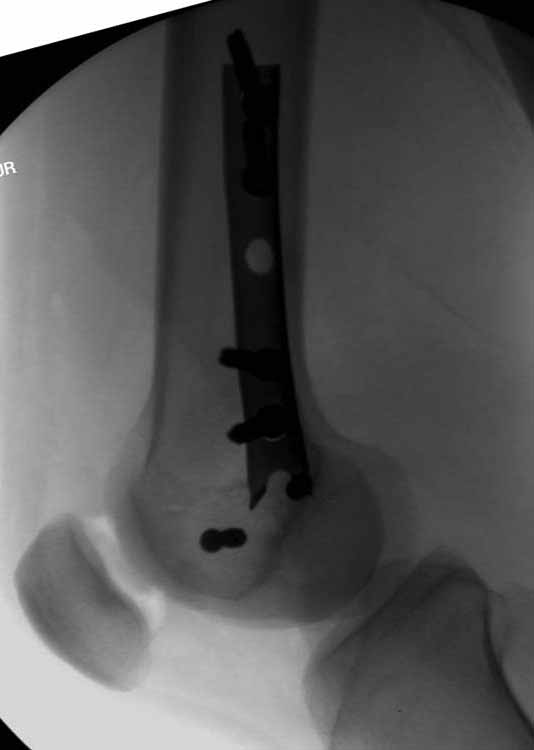

Ответ на эту часть Вашего поста – вложенный файл. Больная оперирована неделю назад по поводу открытого перелома дистального эпиметафиза бедренной кости. После операции она идёт в рентгенкабинет для выполнения послеоперационной контрольной рентгенографии, представленной на слайдах 10 и 11. Узнав, почему её фотографируют, просила передать Вам, Антон, привет.

Мне представляется, что конструкция с максимальными прочностными характеристиками будет иметь вид предложенной во вложенном файле. Такую конфигурацию расположения блокирующих отверстий на дистальном конце имеет стержень для большеберцовой кости фирмы ChM. Для бедренной кости такой стержень мне неизвестен. Поэтому в необходимых случаях (хорошо, что такие случаи встречаются не часто), как вариант, мы используем custom made стержень.

Позволю себе напомнить коллегам ещё раз, что являюсь сторонником антеградного остеосинтеза при переломах дистального эпиметафиза бедренной кости. Такая приверженность основана не на преимуществах внесуставного введения стержня или большем проценте положительных результатов. Она основана на возможности обеспечить блокирование на минимальном расстоянии от суставной поверхности в нескомпрометированной кости и, таким образом стабилизировать максимально низкие переломы. В приведенном Вами случае самый дистальный из блокирующих винтов проведен на расстоянии более 2 см от конца стержня. Из-за того, что к стержню присоединяется кондуктор, на стержне теряется 1-1,5 см его длины, где можно было разместить отверстия для блокирования. И что более важно, вместе с потерянной для этой цели длиной стержня утрачивается для размещения блокировочных винтов, пожалуй, самая ценная часть дистального эпиметафиза бедренной кости. Проблемы дистального блокирования в разных плоскостях, локализации точки ввода стержня при антеградном остеосинтезе – это всё решаемые технические проблемы. Но антеградный остеосинтез низких дистальных переломов бедра при адекватном блокировании в нескомпрометированной кости обеспечивает решение стратегической задачи – стабильный остеосинтез и возможность нагрузки.